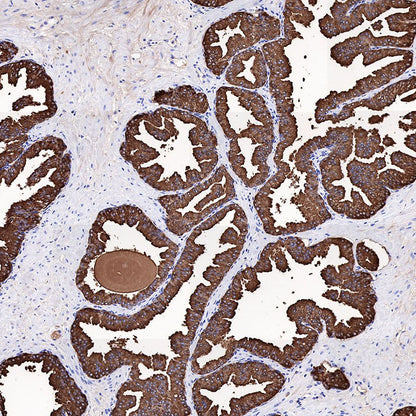

Immunohistochemistry

IHC shows positive staining in paraffin-embedded human prostate cancer. Anti-PSA antibody was used at 1/1000 dilution, followed by a HRP Polymer for Mouse & Rabbit IgG (ready to use). Counterstained with hematoxylin. Heat mediated antigen retrieval with Tris/EDTA buffer pH9.0 was performed before commencing with IHC staining protocol.